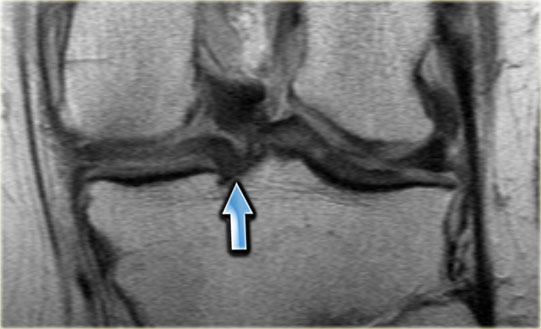

-

Chúng ta bắt đầu với lát cắt ở giữa của khảo sát.

Lưu ý thân sụn chêm bên có kích thước nhỏ với hình dạng bất thường (mũi tên xanh).

Phần bờ trong bị khuyết được nhìn thấy ngay phía ngoài dây chằng chéo trước (mũi tên đỏ). - Phần sụn chêm bị rách di lệch vào trong, tức là phần quai xách, có thể được theo dõi theo hướng ra sau trong hố gian lồi cầu.